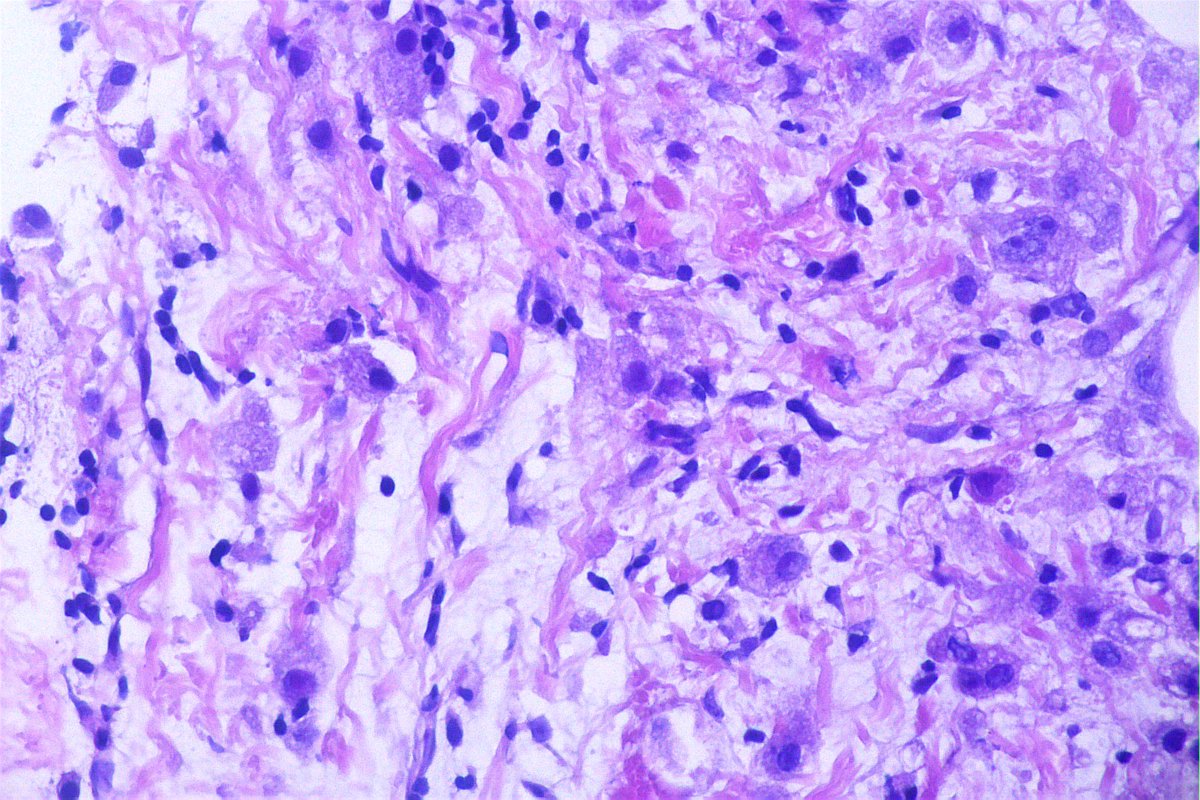

@GeronimoJrLapac

Ger么nimo Jr.

4 months

Synapt and chromo +++ Final Dx: Pit NET.